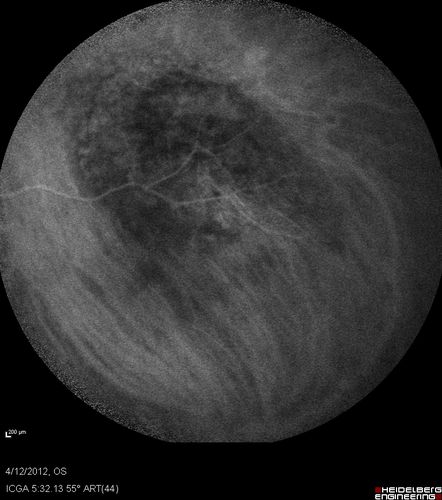

Medium Choroidal Melanoma Left Eye

Melanoma - Choroidal Medium - Macular